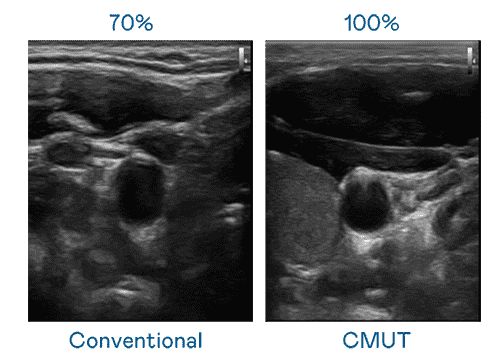

CMUT 技术是一种用电容式微机电元件来产生超音波讯号的技术。。与传统 PZT 压电式技术相比,,,CMUT 频宽增加 30%,,更宽频的超音波讯号让影像解析度大幅提升,,,是实现高影像品质医疗超音波扫描、、促进精准医疗发展的关键技术。。。。

大频宽带来超清晰影像

超音波影像的解析度高低,,首先取决于探头能发出的讯号频宽。。。。尊龙z6 CMUT 可提供高清晰的超音波讯号,,,提供高频宽、、、高灵敏度、、影像纹理细节更高的超音波影像,,,协助医护人员缩短影像判读时间及利用精准的医疗影像进行诊断。。。